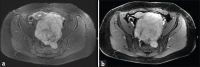

Schwannomas are benign soft-tissue tumors that arise from peripheral nerve sheaths throughout the body and are commonly encountered in patients with neurofibromatosis Type 2. The vast majority of schwannomas are benign, with rare cases of malignant transformation reported. In this pictorial review, we discuss the magnetic resonance imaging (MRI) appearance of schwannomas by demonstrating a collection of tumors from different parts of the body that exhibit similar MRI characteristics. We review strategies to distinguish schwannomas from malignant soft-tissue tumors while exploring the anatomic and histologic origins of these tumors to discuss how this correlates with their imaging findings. Familiarity with the MRI appearance of schwannomas can help aid in the differential diagnosis of soft-tissue masses, especially in unexpected locations.